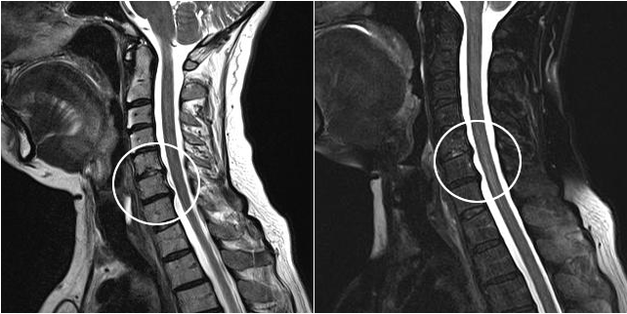

Modern diagnostic methods include MRI and CT, which allow the most accurate study of the processes of destruction of cartilage and bone tissue.Also, with the help of this technique, it is convenient to diagnose hernias and other soft tissue defects near the source of the disease.